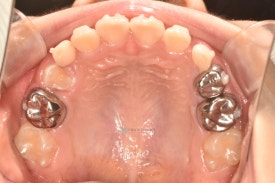

치료 전 - 위아래 심한 공간 부족이 관찰됩니다.

기존 교정장치와 같은 철사 찔림이 없고 확장과 치아배열이 동시에 잘되는 투명교정장치입니다. 착용한 상태에서도 거의 티나지 않아 아이들이 좋아합니다.😁

치료 전 - 위아래 심한 공간 부족이 관찰됩니다.기존 교정장치와 같은 철사 찔림이 없고 확장과 치아배열이 동시에 잘되는 투명교정장치입니다. 착용한 상태에서도 거의 티나지 않아 아이들이 좋아합니다.😁